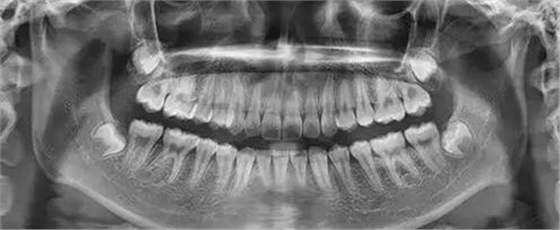

為了幫助矯正醫(yī)生準(zhǔn)確的分析患者的具體情況,醫(yī)生需要幫準(zhǔn)備矯正的患者拍攝全景牙片以及頭顱側(cè)位片。

作用:通過(guò)全景片我們可以看到牙齒的數(shù)目是否有異常情況(例如:主要是頜骨內(nèi)有無(wú)多生牙,埋伏牙等),牙根的情況(如:包括形態(tài),位置,牙根有無(wú)吸收等),牙槽骨的情況,牙周組織的健康狀況,髁狀突的狀態(tài)等。